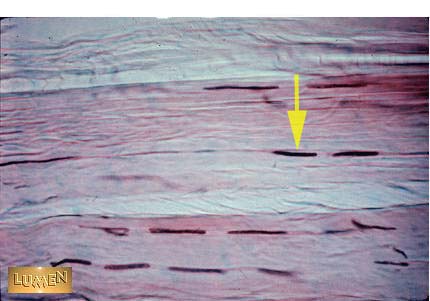

Q1 Identify the cell?

Q2 What kind of tissue is this? Be specific.

Answer 1

Fibroblast

Answer 2

Dense Regular Connective Tissue